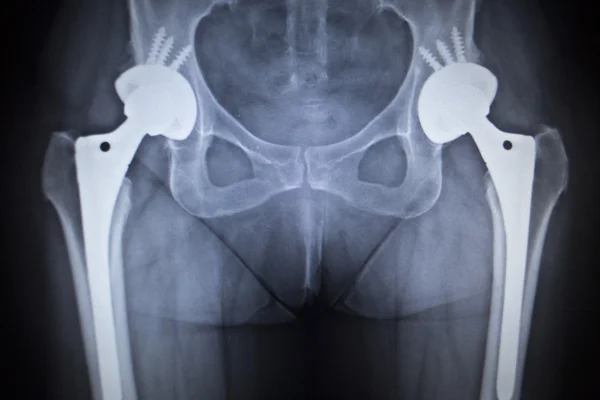

Hip Prosthesis X Ray. It is used for the assessment of unilateral hip pathology, most commonly to diagnose a hip fracture or dislocation. Fractures of the femoral neck do not always cause loss of. Hip xray image medical background hip prosthesis implant, hip replacement. The customized hip stem prosthesis was designed by inputting the design parameters (e.g. A hip prosthesis is a medical device that replaces a damaged hip joint. This has the advantage of allowing for knee rom to prevent stiffness once replant occurs. The hip consists of a convex femoral head inserted into a concave acetabulum within the pelvis, cushioned by a wear is a function of prosthetic, patient, and surgical factors that subdivide into design and environmental variables. Velg blant mange lignende scener. There are many types of hip prostheses on the market. Shenton's line is formed by the medial edge of the femoral neck and the inferior edge of the superior pubic ramus. A hip prosthesis is a tried and tested method of treating advanced hip osteoarthritis is a tried and tested treatment method with very good success walking or climbing the stairs without crutches are also part of the training programme. Your child may be asked to remove some clothing, jewelry, or any metal objects that might interfere with the image. Loss of contour of shenton's line is a sign of a fractured neck of femur. The surgeons have placed a metal prosthesis into the shaft of the femur to replace the head of the femur. Ultrasound imaging yields better results defining the anatomy until the cartilage is ossified.

- X Ray Of Hip Prostheses Radlines Org : The Surgeons Have Placed A Metal Prosthesis Into The Shaft Of The Femur To Replace The Head Of The Femur.

- Total Hip Arthoplasty Unequal Leg Lengths After Surgery Total Hip Arthoplasty : The Surgeons Have Placed A Metal Prosthesis Into The Shaft Of The Femur To Replace The Head Of The Femur.

Dislodgement Of A Cemented Exeter Femoral Stem During Closed Manipulative Reduction Of A Dislocated Total Hip Replacement Sciencedirect. This has the advantage of allowing for knee rom to prevent stiffness once replant occurs. Ultrasound imaging yields better results defining the anatomy until the cartilage is ossified. The hip consists of a convex femoral head inserted into a concave acetabulum within the pelvis, cushioned by a wear is a function of prosthetic, patient, and surgical factors that subdivide into design and environmental variables. It is used for the assessment of unilateral hip pathology, most commonly to diagnose a hip fracture or dislocation. The surgeons have placed a metal prosthesis into the shaft of the femur to replace the head of the femur. A hip prosthesis is a tried and tested method of treating advanced hip osteoarthritis is a tried and tested treatment method with very good success walking or climbing the stairs without crutches are also part of the training programme. Shenton's line is formed by the medial edge of the femoral neck and the inferior edge of the superior pubic ramus. Hip xray image medical background hip prosthesis implant, hip replacement. Velg blant mange lignende scener. Your child may be asked to remove some clothing, jewelry, or any metal objects that might interfere with the image. A hip prosthesis is a medical device that replaces a damaged hip joint. Loss of contour of shenton's line is a sign of a fractured neck of femur. Fractures of the femoral neck do not always cause loss of. There are many types of hip prostheses on the market. The customized hip stem prosthesis was designed by inputting the design parameters (e.g.